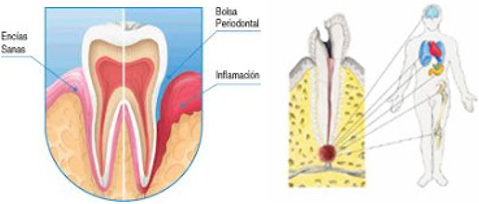

Generalmente, se ha creído que los dientes son partes aisladas en comparación con el resto de órganos que compone nuestro cuerpo, olvidando que el órgano dental forma parte del sistema estomatognático, sin embargo, varios estudios en la actualidad han demostrado que los problemas que se ocasionan en las piezas dentales provoca alteraciones a nivel sistémico un claro ejemplo es el estudio realizado por Lamonte en 2017, donde encontró una marcada relación entre la pérdida de las piezas dentales y las enfermedades cardiovasculares, así como la mortalidad de mujeres de avanzada edad, otro ejemplo claro es la marcada relación que existe entre la uveítis (infección a nivel ocular) y los problemas endo-periodontales según lo encontrado por Peña-Sisto M. en la ciudad Santiago de Cuba y así podemos citar muchos más estudios que relacionan los problemas médicos con los problemas dentales, el caso más comentado por los profesionales de la salud dental es el alto riesgo de tener una endocarditis bacteriana por la falta de precauciones durante el tratamiento dental.

Hay una asociación estrecha de varios órganos con las piezas dentales, el grupo de los incisivos se encuentran relacionados con la vejiga y los riñones, así como los dolores referidos sobre todo a nivel de la frente, mientras que a los caninos se asocia con el hígado, los premolares con el pulmón y el colon, por último, los molares se conjugan con el estómago, bazo y el páncreas.

Los diferentes dolores en cada pieza dental exteriorizan patologías tales como: gastritis, bronquitis, neumonía, amigdalitis, entre otras. Las piezas dentales no solo indican los problemas que el organismo tiene que soportar, sino puede indicar el carácter del sujeto y esto va ir de acuerdo a la apariencia de los órganos dentales.

- Bolsas periodentales profundas